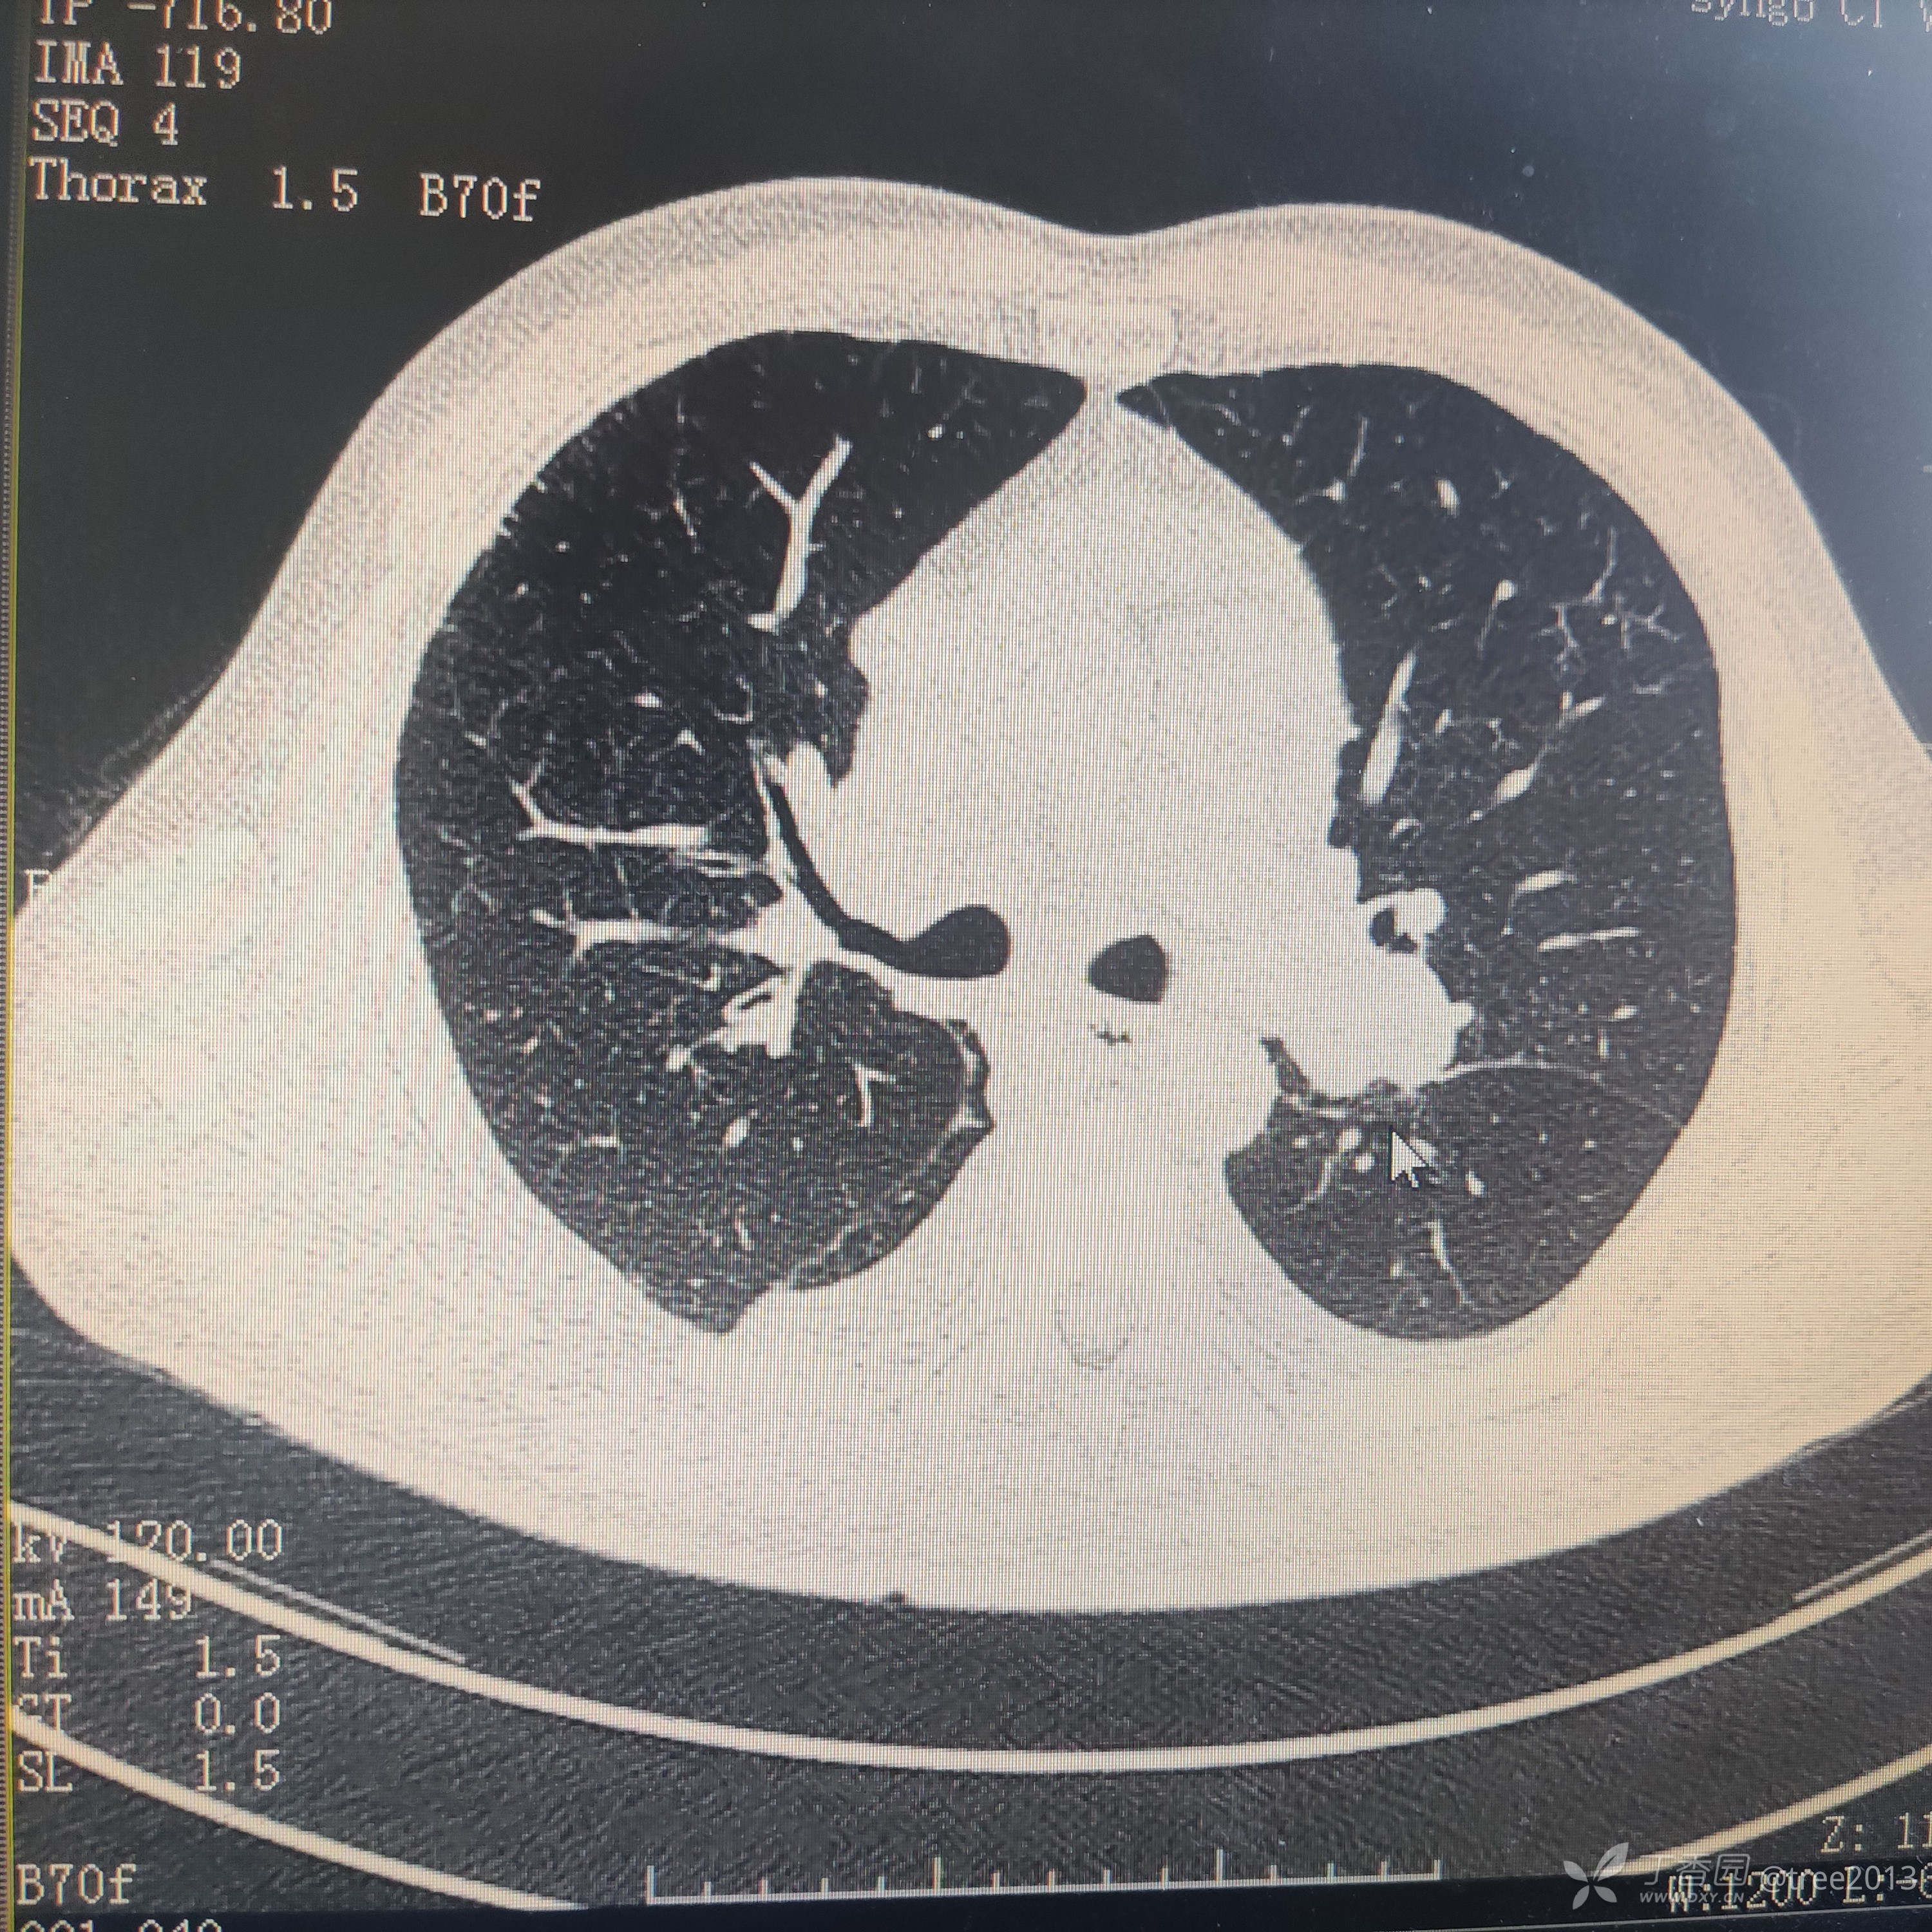

胸部CT:

诊断:肺部恶性肿瘤伴多大转移 心包积液 胸腔积液